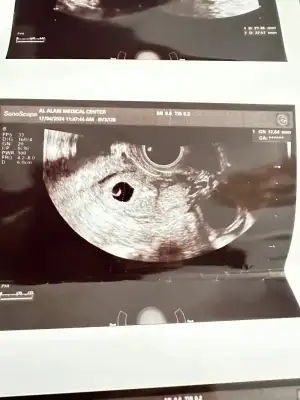

Merhaba bebegi gorup kalp atisini diymaniza cok sevindim. Adetiniz kac gun gectikten sonra gordunuz bebeginizi. Benim adet gunumun gecmesinin 13.gunu 6 haftalik gorunuyor kesem 12mm olmus yolk var ama icinde bebek yok.. yardim eder misiniz sizinde oyle miydi? Saglikla bebginizi kucaginiza almanizi diliyorum. 💜

Eklentiler

• EB476262-F46E-419C-8979-42249D97F513.webp

EB476262-F46E-419C-8979-42249D97F513.webp

35 KB · Görüntüleme: 237